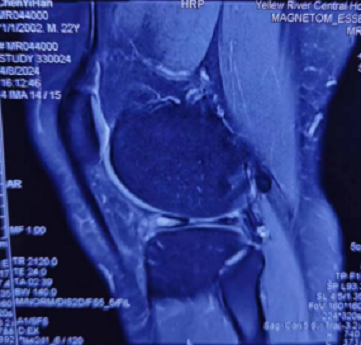

在朋友的介绍下来到郑州大学第五附属医院骨科三病区诊治。接诊的主任医师闫鹏仔细询问患者病史并进行查体,考虑半月板损伤,遂嘱患者进行磁共振检查。MRI检查结果显示,左膝关节外侧半月板撕裂。经过仔细认真的沟通,患者接受了关节镜微创手术治疗。

▲ 术前左膝MRI